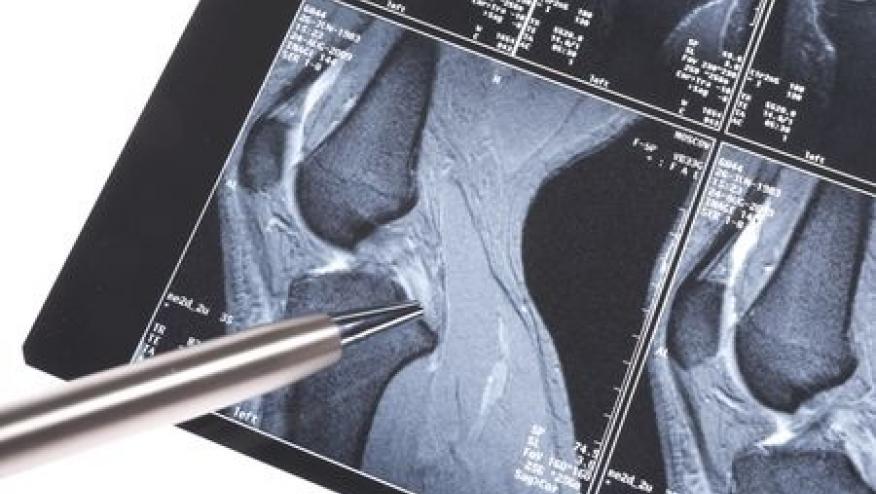

MRI of the hands were scored for synovitis, osteitis, tenosynovitis and periarticular inflammation. Psoriasis patients underwent quantitative CT to detect erosions and enthesitis.

Nearly half (47%) of psoriasis patients had at least one inflammatory lesion on MRI, with synovitis being the most prevalent inflammatory lesion (38%), followed by osteitis (11%), tenosynovitis (4%) and periarticular inflammation (4%). The risk for developing PsA was as high as 60% if patients had subclinical synovitis and arthralgia, but only 13% in those without either.